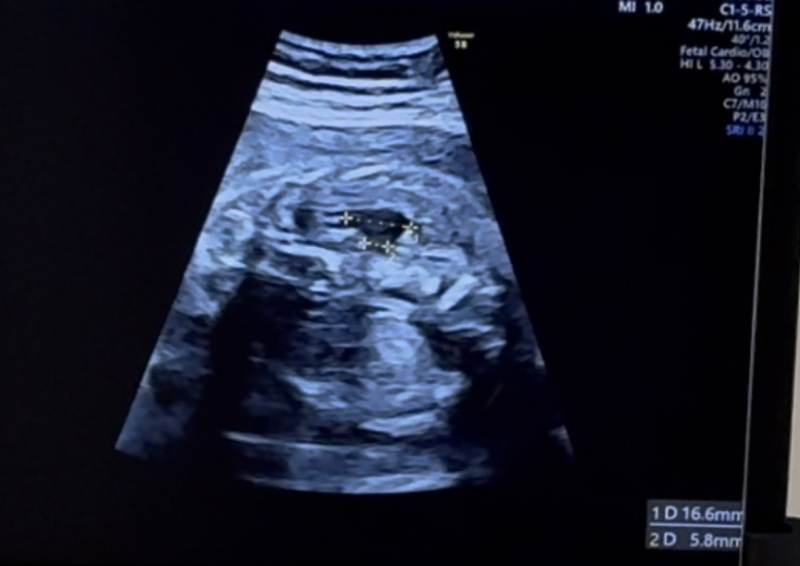

26w5dの健診で、初めて右側の腎臓が腫れているから、水腎症かもしれないと言われました。

エコー写真がその時のサイズです。

上の方が16.6mm、下の方が5.8mmになっています。